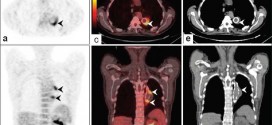

CANCER PULMONAR DE CELULAS NO PEQUEÑAS (NSCLC)

El cáncer pulmonar de células no pequeñas (NSCLC). Tus pulmones son los órganos más grandes de tu cuerpo y trabajan con tu aparato respiratorio para permitirte inspirar aire fresco, deshacerte del aire viciado e incluso hablar. Tus pulmones están en tu tórax y son tan grandes que ocupan la mayor parte del espacio disponible. Tienes dos pulmones, pero no son …